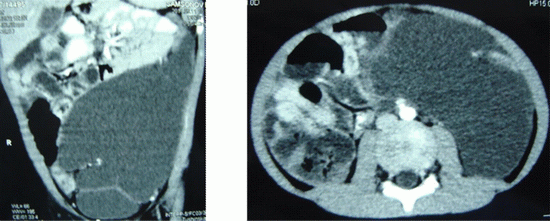

ЛА забрюшинного пространства

мальчик, 5 лет